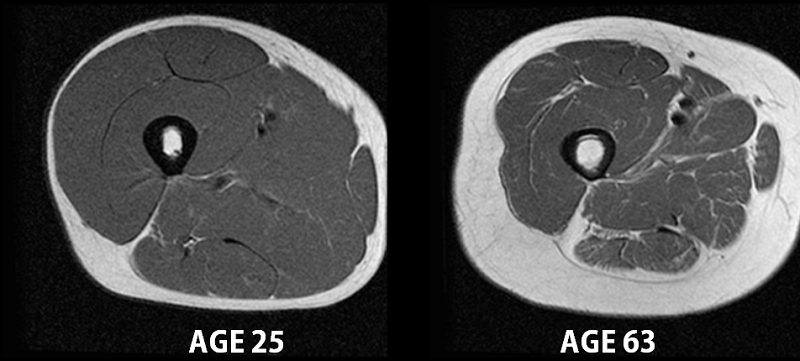

Au niveau cellulaire, la sarcopénie se traduit par une diminution importante du pool protéique musculaire squelettique, ce qui se traduit dans les faits par une perte progressive de masse musculaire.

Les fibres musculaires diminuent tant en nombre qu’en taille, conduisant ainsi à la diminution de la surface de section musculaire (Waters et al., 2000).

L’évaluation de la sarcopénie passe principalement par des mesures de composition corporelle, permettant de calculer la masse grasse et la masse maigre.

Ces mesures permettent de mettre en évidence la fonte musculaire.

Il est à noter que la fonte musculaire peut être masquée par une augmentation concomitante de la masse grasse : ainsi la simple mesure du poids ne suffit pas à caractériser une sarcopénie (Gallagher et al., 2000).